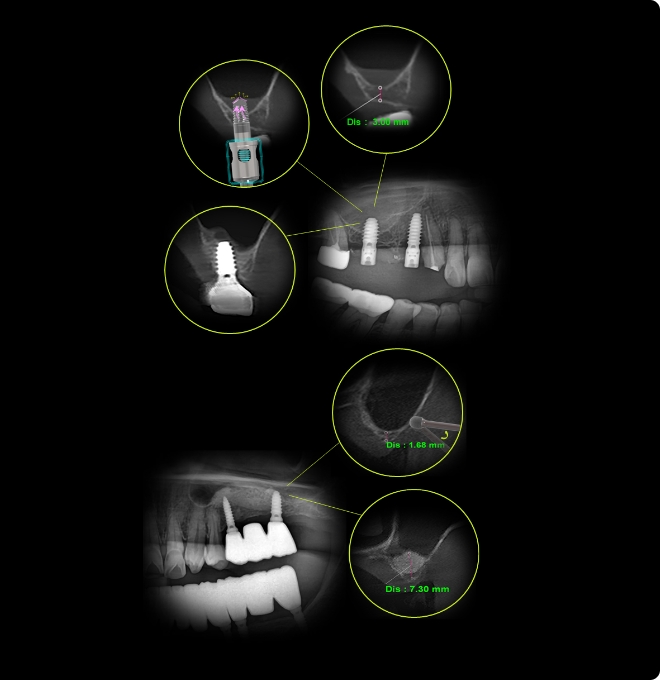

Concept 4SurgerySinus Simple

Streamlined Steps - Reliable Outcomes - Enhanced Safety

- Versatile Application

The single kit (DASK Simple) supports multiple maxillary sinus surgery approaches, including both crestal and lateral techniques, enables practitioners to adapt easily to diverse clinical situations while minimizing patient discomfort.

- Enhanced Workflow

The simple kit design minimizes preparation time, enhances surgical efficiency and provides patients with a faster, more comfortable treatment.

- Safety-Focused Design

Ergonomically designed drills minimize tissue damage, ensuring safer surgical and supporting faster postoperative recovery for patients.